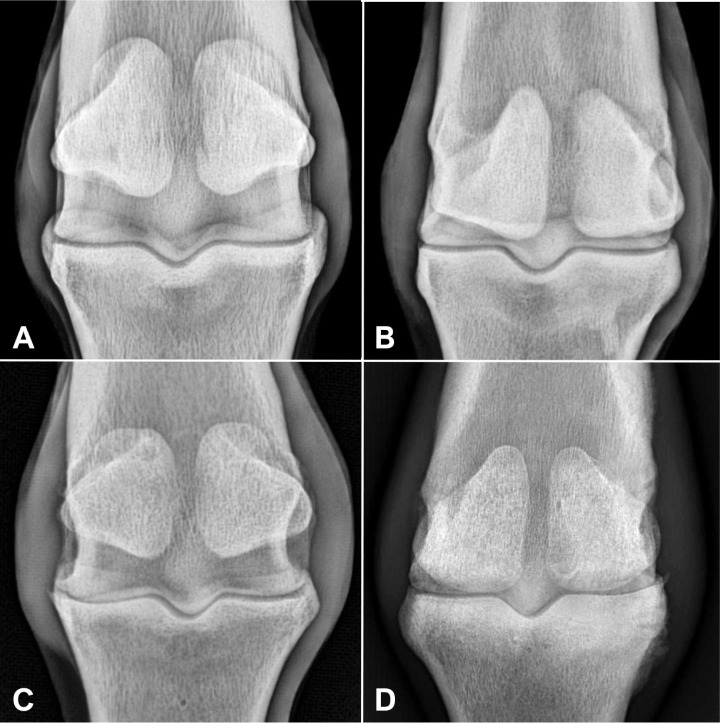

骨关节炎(OA)是马的一种常见病,会导致骨小梁结构和放射纹理发生变化。虽然分形维度(FD)和裂隙度已被用于量化人类的这些变化,但它们在马匹中的应用仍处于起步阶段。本研究评估了分形维度、骨面积分数(BA/TA)和裂隙度在量化近节指骨(P1)骨小梁差异中的应用,共对 50 例不同 OA 程度的马掌指关节进行了射线检查。在背侧视图中,在近端骨骺的骨小梁、P1矢状沟的内侧和外侧定义了感兴趣区域。在严重OA马的内侧观察到较低的BA/TA值(P=0.003)。不同OA程度的马在FD和裂隙度方面没有明显差异(P>0.1)。FD、BA/TA和裂隙度不能有效识别不同掌指关节OA程度马匹P1骨小梁的放射纹理变化。

Osteoarthritis (OA) is a prevalent condition in horses, leading to changes in trabecular bone structure and radiographic texture. Although fractal dimension (FD) and lacunarity have been applied to quantify these changes in humans, their application in horses remains nascent. This study evaluated the use of FD, bone area fraction (BA/TA), and lacunarity in quantifying trabecular bone differences in the proximal phalanx (P1) in 50 radiographic examinations of equine metacarpophalangeal joints with varying OA degrees. In the dorsopalmar view, regions of interest were defined in the trabecular bone of the proximal epiphysis, medial and lateral to the sagittal groove of P1. Lower BA/TA values were observed medially in horses with severe OA (P=0.003). No significant differences in FD and lacunarity were found across OA degrees (P>0.1). FD, BA/TA, and lacunarity were not effective in identifying radiographic texture changes in the P1 trabecular bone in horses with different metacarpophalangeal OA degrees.